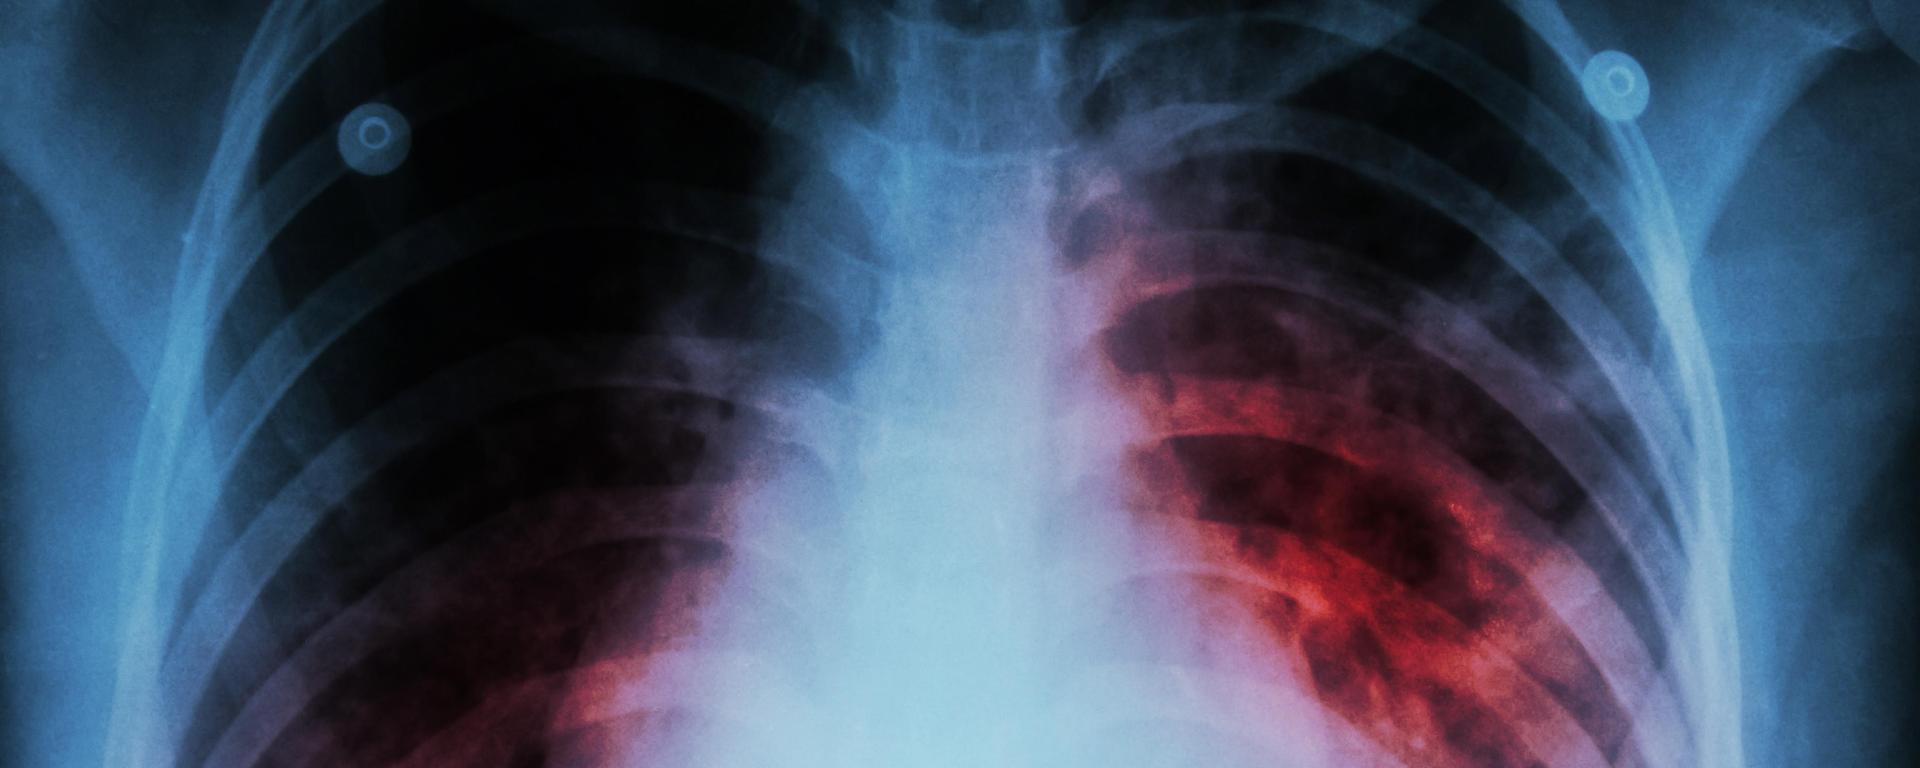

La tuberculosis es una enfermedad contagiosa, que es producida por un bacilo llamado mycobacterium, el cual es transmitido a través del aire y que su principal característica es la aparición de una especie de nódulos en los tejidos que son atacados por el microorganismo.

Es una patología muy grave, que daña rápidamente cualquier órgano del cuerpo, principalmente los pulmones, provocando síntomas como tos, que puede tener presencia de sangre y una notable disminución de peso.